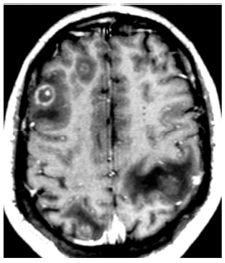

Um homem de 24 anos, portador de infecção por HIV é investigado por apresentar história de febre e rebaixamento do nível de

consciência. A ressonância nuclear magnética mostrou:

Foi realizado um mapeamento cerebral com Thallium-201 que foi negativo para captação do isótopo. Esses achados, somados aos dados epidemiológicos do Brasil permitem afirmar, com alta probabilidade, tratar-se de